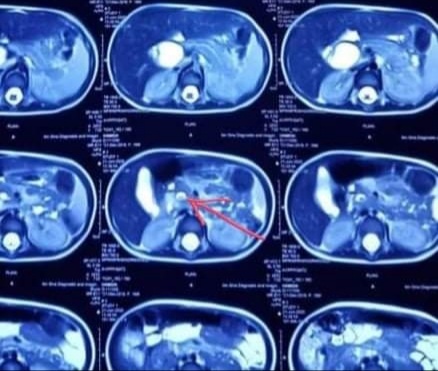

Laboratory data showed the following values: Hb-8.4 g/l, microcytic hypochromic anemia, WBC-8.2×10˄3/mL, S. bilirubin was 3.9mg/dl with dominant direct bilirubin, SGPT 349 U/L, Anti HAV IgM: negative. Serum amylase 306u/l, S. lipase 2270 U/L, electrolyte was normal. Abdominal USG showed-fusiform dilatation of CBD measuring about (4.1×1.7cm) cystic duct dilated. There were multiple granules mobile echogenic structure without shadow seen in lumen of the CBD. MRCP showed fusiform dilatation (2.2cm) of proximal CBD involving common hepatic duct over 3.5 cm segment (Figure 1). Distal CBD was mildly (1cm) dilated containing 2 tiny flow void suggesting calculus (0.5cm) seen with lumen of distal CBD (Figure 2). Pancreatic duct was visualized & mildly dilated.

Figure 1: MRCP showing fusiform dilatation of proximal CBD involving common hepatic duct.

Figure 2: Distal CBD with signal void structure within suggestive of stones.